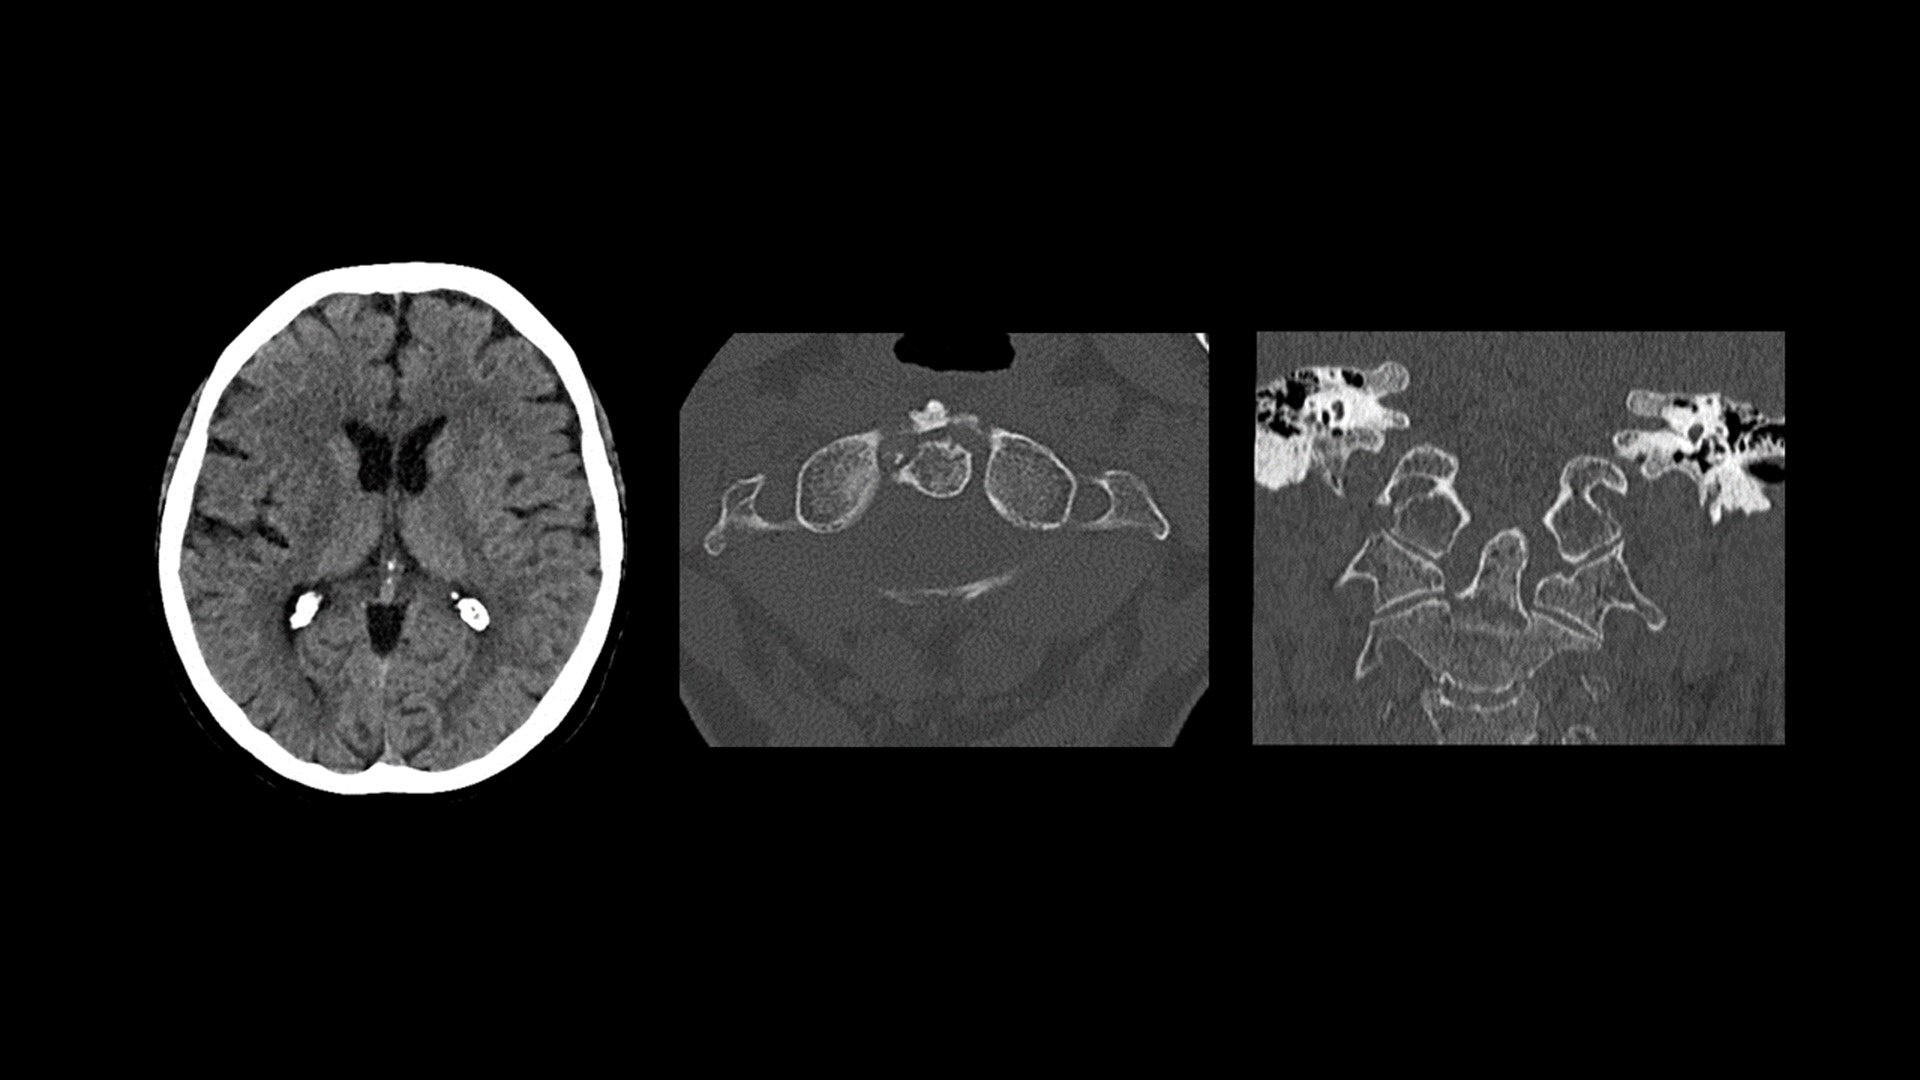

Cardiac CT has become a front-line, non-invasive imaging tool for diagnosing, treatment planning and monitoring of cardiovascular disease

Healthcare providers are striving to improve patient health but are struggling with increasingly complex exams, insufficient or inexperienced staff, and operational and capital efficiency. Revolution™ Vibe, designed to deliver leading-edge technology, features advanced cardiovascular capability. It improves patient access and operational efficiency, prioritizes patient care and supports your facility's growth with lower lifecycle costs.

Unlimited 1-Beat Cardiac is designed to provide consistent, high-quality imaging for accurate diagnoses, even in challenging patients with atrial fibrillation, breath-holding difficulties, heavily calcified coronaries, in-stent restenosis, and situations where an ECG trace is unavailable.